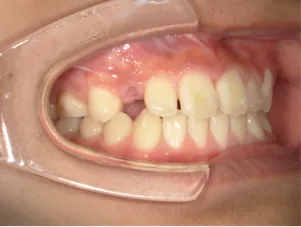

治療後⑤中3:咬合治療終了 マルチブラケット法の期間は9か月